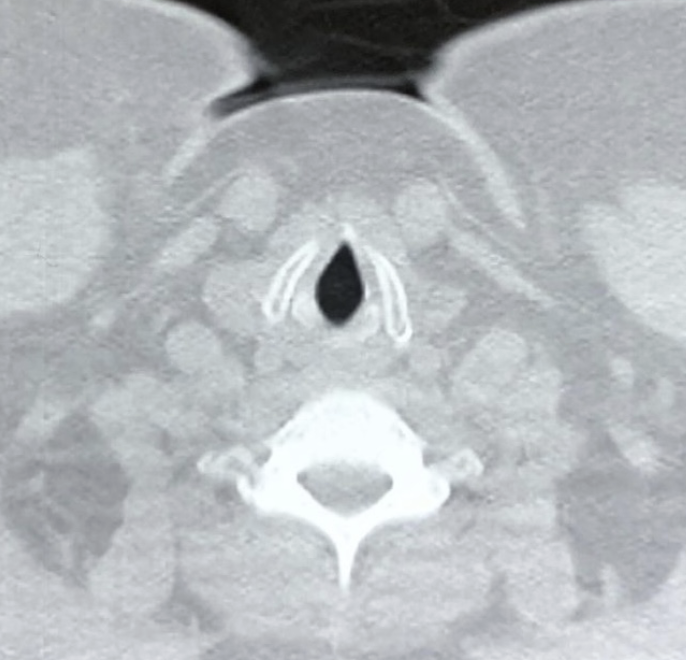

TAC / AXIAL

NIVEL GLÓTICO:

CUERDAS VOCALES

Y CARTÍLAGO

TIROIDES

Presbilaringe: cartilago tiroides calcificado